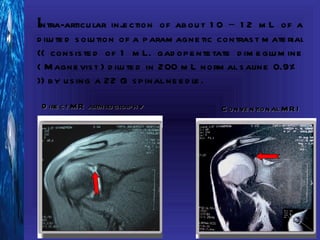

Intra-articu lar inje ction of ab ou t 1 0 – 1 2 m L of a

d ilu te d s olu tion of a p aram agne tic contras t m ate rial

(( cons is te d of 1 m L. gad op e nte tate d im e glu m ine

( M agne vis t ) d ilu te d in 200 m L norm al s aline 0.9%

)) b y u s ing a 22 G s p inal ne e d le .

D ire ct M R arth rograp h y              C onve ntional M R I